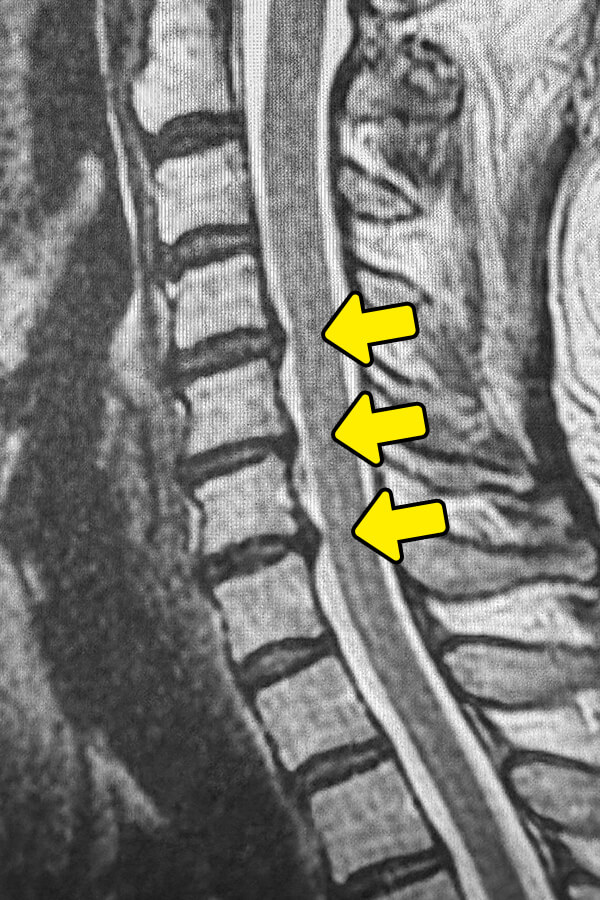

3年前に追突事故に遭われてから後頚部の痛みが持続している状態です。事故後は1年間のリハビリを行われましたが、ほとんど改善が無いまま現在に至っています。頸部のMRI検査となります。C4/5、C5/6、C6/7椎間板に変形とヘルニアが見られます。症状からも頚椎症と診断されます。頸椎椎間板に対してAnnulargram検査を行ったところ、繊維輪損傷が確認されたのでディスクシール治療を行いました。治療直後は頸部の違和感を感じられていましたが、後頚部の痛みは半減しており治療効果が期待できます。

椎間板の高さの減少、骨棘の形成、椎間孔の狭小化を確認 - MRI検査

椎間板・靭帯の状態、脊柱管の狭窄度、脊髄・神経根の圧迫状態を詳細に確認

頚椎症の診断において最も重要なのはMRI検査です。レントゲンで骨棘や椎間板の変性は確認できますが、脊髄や神経根の圧迫状態はMRIでなければ正確に評価できません。当院の大阪本院にはMRI設備を備えており、院内で撮影が可能です。当院ではMRI画像で来院前に治療の可否が分かる無料画像相談を行っておりますので、是非ご利用ください。